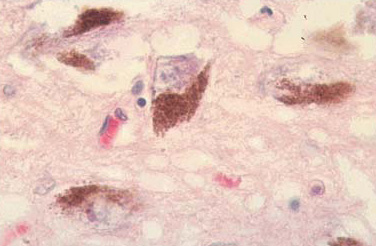

Neuromelanin (brown) in dopamine neurons. Source: Schatz